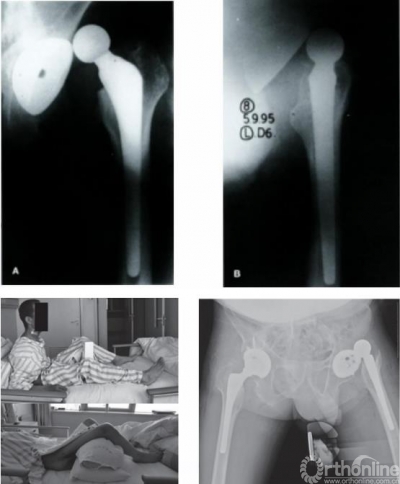

图7 AS引起THA术后脱位病例

手术时可根据后倾角度调整髋臼假体置入角度,减小外展与前倾角,防止术后脱位,增加站立位髋关节稳定性的同时,减少了假体与骨的接触面积,以适应变化的脊柱-骨盆力线,避免术后出现髋臼假体过度前倾,以及站立位时发生后方撞击、前方不稳甚至前脱位等并发症。对于合并脊柱后凸畸形的AS患者,除非畸形过于严重,应首选脊柱矫形术,再行THA。